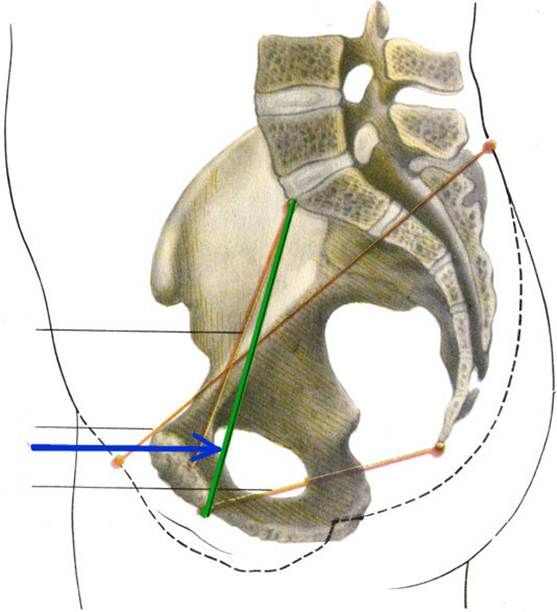

S: Стрелка указывает на Conjugata vera

S: Стрелка указывает на Conjugata diagonalis

S: Стрелка указывает на lig. Sacrospinale

S: Стрелка указывает на лобковый симфиз (русский язык).

S: Стрелка указывает на art. sacroiliaca (латинский язык).

S: Стрелка указывает на foramen ishiadicum majus

S: Стрелка указывает на foramen ishiadicum minus

S: Стрелка указывает на lig. Sacroiliaca posteriora

S: Стрелка указывает на lig. Sacrococcygeum anterius

S: Стрелка указывает на membrana obturatoria (латинский язык).